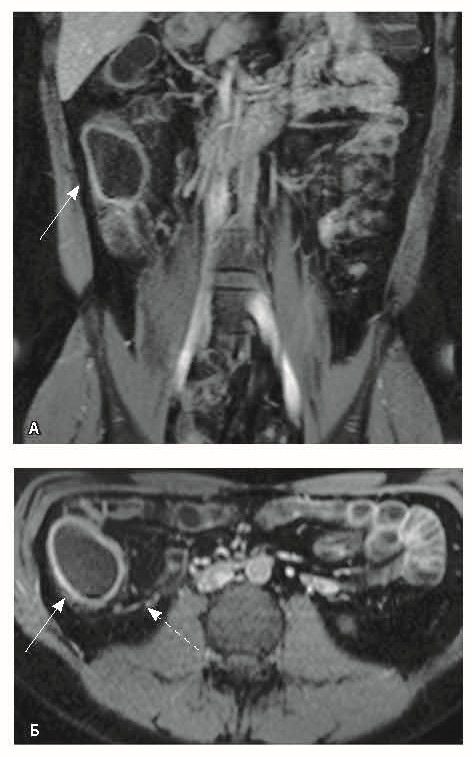

Рис. 2. Магнитно-резонансная энтерография, Т2-взвешенное изображение: А, В – фронтальная проекция; Б – аксиальная проекция. Наблюдается отсутствие гаустрации в восходящем отделе ободочной кишки, утолщение ее стенки до 5 мм (стрелка), снижение магнитно-резонансного сигнала от прилежащих отделов клетчатки, ее неоднородность (пунктирная стрелка), увеличение лимфатических узлов до 6 см в диаметре по ходу сигмовидной кишки (стрелки)